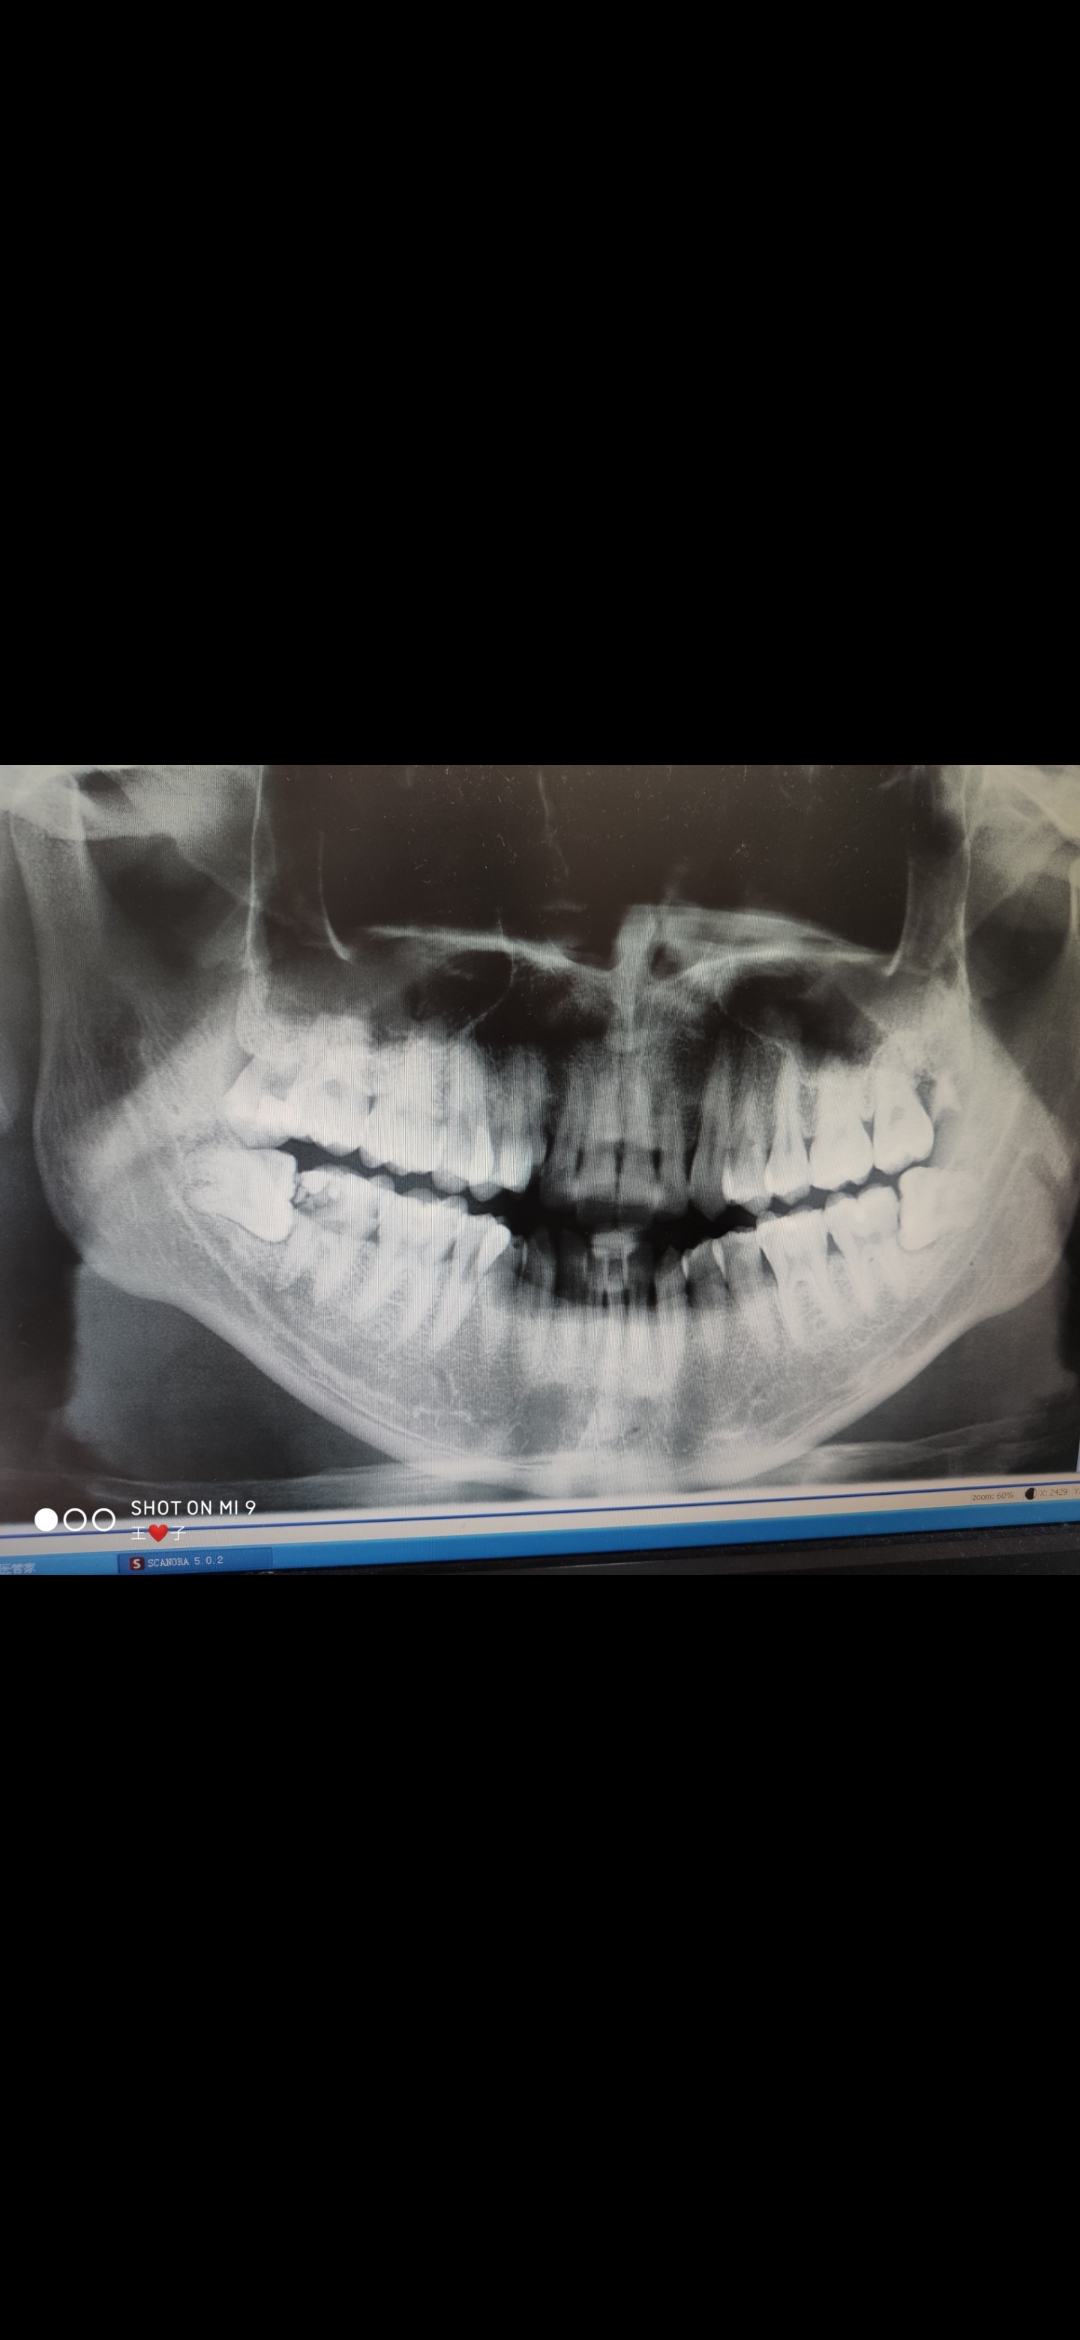

根据口腔颌面部左右对称、颌骨牙弓呈弓形等解剖特点而设计的三轴固定连续转换的弧面断层摄影,观察全口牙齿发育情况以及上下颌骨情况。